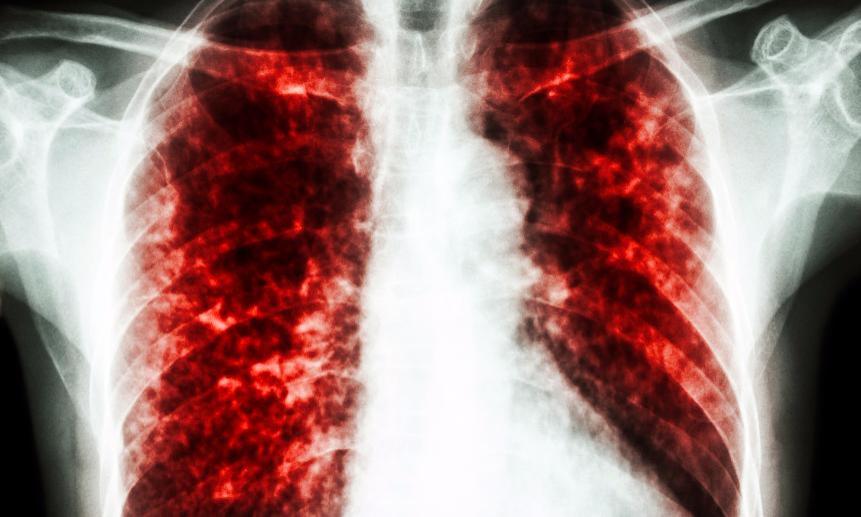

Современные методы лечения туберкулеза